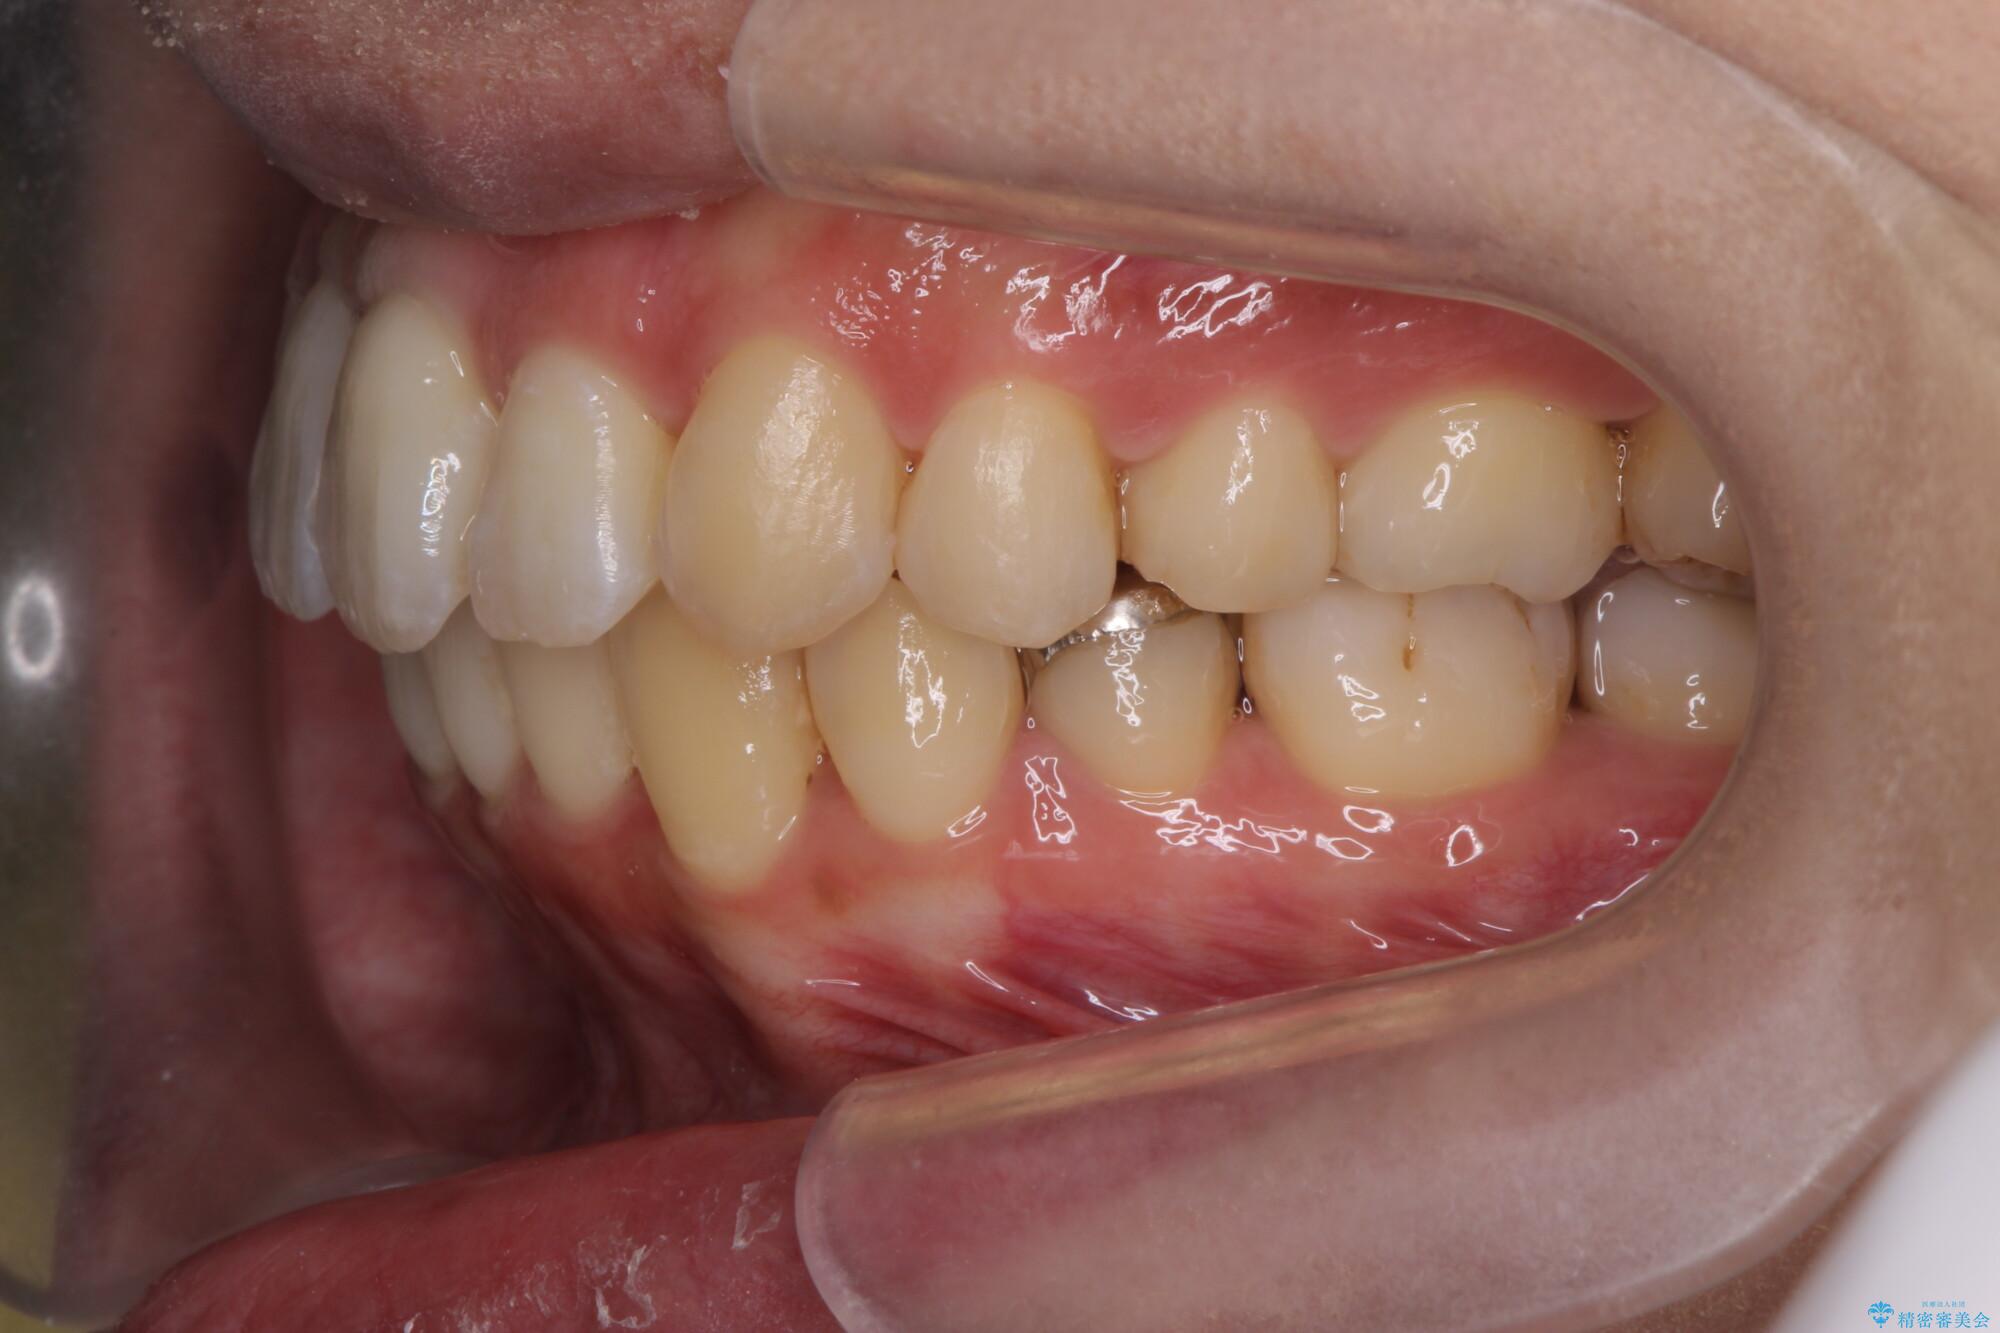

前歯のガタつきの改善を主訴にご来院されました。 特に犬歯の傾きが気になるとのことでした。

犬歯がかなり手前に傾いていましたが、ガタつきはそれほど強くないため非抜歯でマウスピース矯正が可能と判断しました。

治療中

気になる犬歯のガタつきをマウスピース矯正で改善 治療中画像 気になる犬歯のガタつきをマウスピース矯正で改善 治療中画像 気になる犬歯のガタつきをマウスピース矯正で改善 治療中画像 気になる犬歯のガタつきをマウスピース矯正で改善 治療中画像